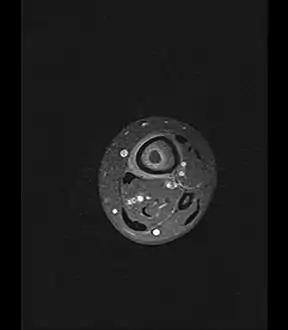

Fat saturated STIR (short tau inversion recovery) image showing hyperintense edema in the calf musculature, marrow edema, and subperiosteal pus. The intramedullary abscess cavity is hyperintense as well.